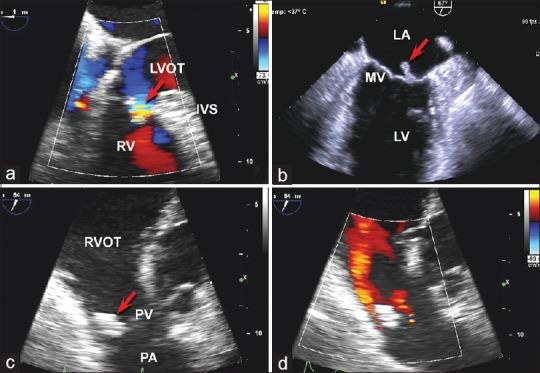

A 63-year-old man presented with generalized fatigue, chills, malaise, dyspnea, intermittent fevers, and 50-pound weight loss of 4 months' duration. Blood cultures were positive for pan-sensitive Streptococcus anginosus. Transesophageal echocardiography showed an 11 mm × 3 mm mobile mass attached to the mitral valve, a 16 mm × 16 mm mobile mass attached to the pulmonary valve, and a small membranous ventricular septal defect. The patient received 12 weeks of intravenous (IV) antibiotics with eventual resolution of the masses. Multi-valve endocarditis involving both the left and right chambers is rarely reported without prior history of IV drug use or infective endocarditis. Our case emphasizes the importance of careful assessment for ventricular septal defects or extra-cardiac shunts in individuals who present with simultaneous right and left-sided endocarditis.

一名63岁男性,出现全身乏力、寒战、不适、呼吸困难、间歇性发热,4个月内体重减轻50磅。血培养显示咽峡炎链球菌全敏感。经食管超声心动图显示二尖瓣上附着一个11mm×3mm的活动肿物,肺动脉瓣上附着一个16mm×16mm的活动肿物,以及一个小的膜周部室间隔缺损。患者接受了12周的静脉抗生素治疗,肿物最终消退。在没有静脉药物使用史或感染性心内膜炎病史的情况下,累及左右心室的多瓣膜心内膜炎鲜有报道。我们的病例强调了对于同时出现右侧和左侧心内膜炎的个体,仔细评估室间隔缺损或心外分流的重要性。